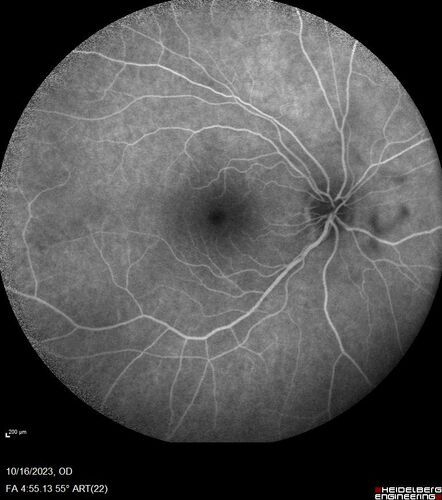

Central Retinal Vein Occlusion with cilioretinal artery occlusion

63 year old female who lost vision in the left eye 2 days ago. She was in the emergency room and had a lot of tests done which were all reportedly normal. The right eye is OK.

VA OD: Dcc20/25 NccJ2

VA OS: Dcc20/200-1 PHNI Ncc20/400-1

IOP: TP: OD:11 OS:12